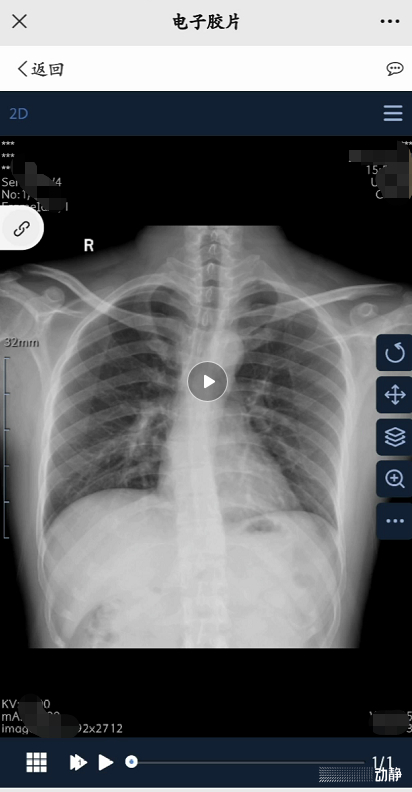

“云胶片”告别了传统“塑料袋+传统医用胶片”模式,患者通过手机扫描相关二维码,即可查看检查报告及全部DICOM原始三维影像。“云胶片”三维影像(3D影像)不仅能为医生下诊断提供全方位可视影像,还能为远程会诊、异地转诊和分级诊疗提供更全面的技术支撑,简化了取片就诊流程,改善了就医体验。此外,患者能够在手机端发起胶片共享,并能设置共享有效期,在方便患者使用的同时也保证了数据安全。

记者近日从贵州省人民医院了解到,该院“云胶片”服务已正式上线,医生只需在开单时勾选电子胶片,患者缴费后即可在检查后扫描纸质报告上的二维码或通过微信公众号查看原始三维影像。

据了解,“云胶片”基于移动互联网和云储存技术,助力医院全面开启医疗影像智慧服务云模式,具有检查结果互认、资料共享等优点,医生能获取患者当前全部检查数据和完整的历史检查数据,有利于影像应用到临床,便于健康管理等。